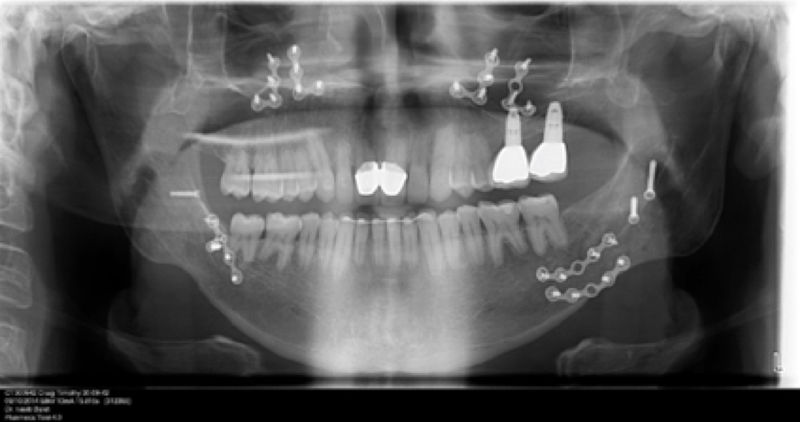

Son estructuras de titanio las cuales se colocan en el hueso y se utilizan para soportar coronas, prótesis fijas, removibles y totales. La colocación de los implantes se hacen previo análisis tomográfico.

Implante fracasado, extracción, carillas, coronas y prótesis fija.

Cirugía ortognática, implantes, carillas y coronas,